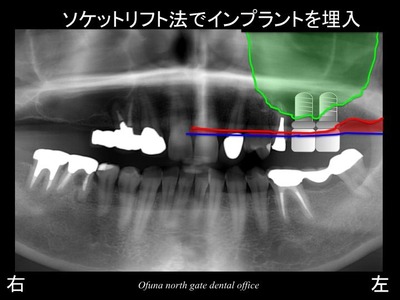

今回の症例もソケットリフト法を応用してインプラント治療を行う治療計画を立てました。

以下がソケットリフト法でインプラントを埋入した直後です。

ソケットリフト法を行った部位を拡大して見てみましょう!

この拡大レントゲンに

先程の骨のラインと上顎洞の線を記入してみます。

さらにこのレントゲン写真に

ソケットリフト法を行った後の上顎洞を書いてみます。

青線が挙上された上顎洞の位置です。

挙上された上顎洞の内部には人工の骨(βーTCP)が入っています。